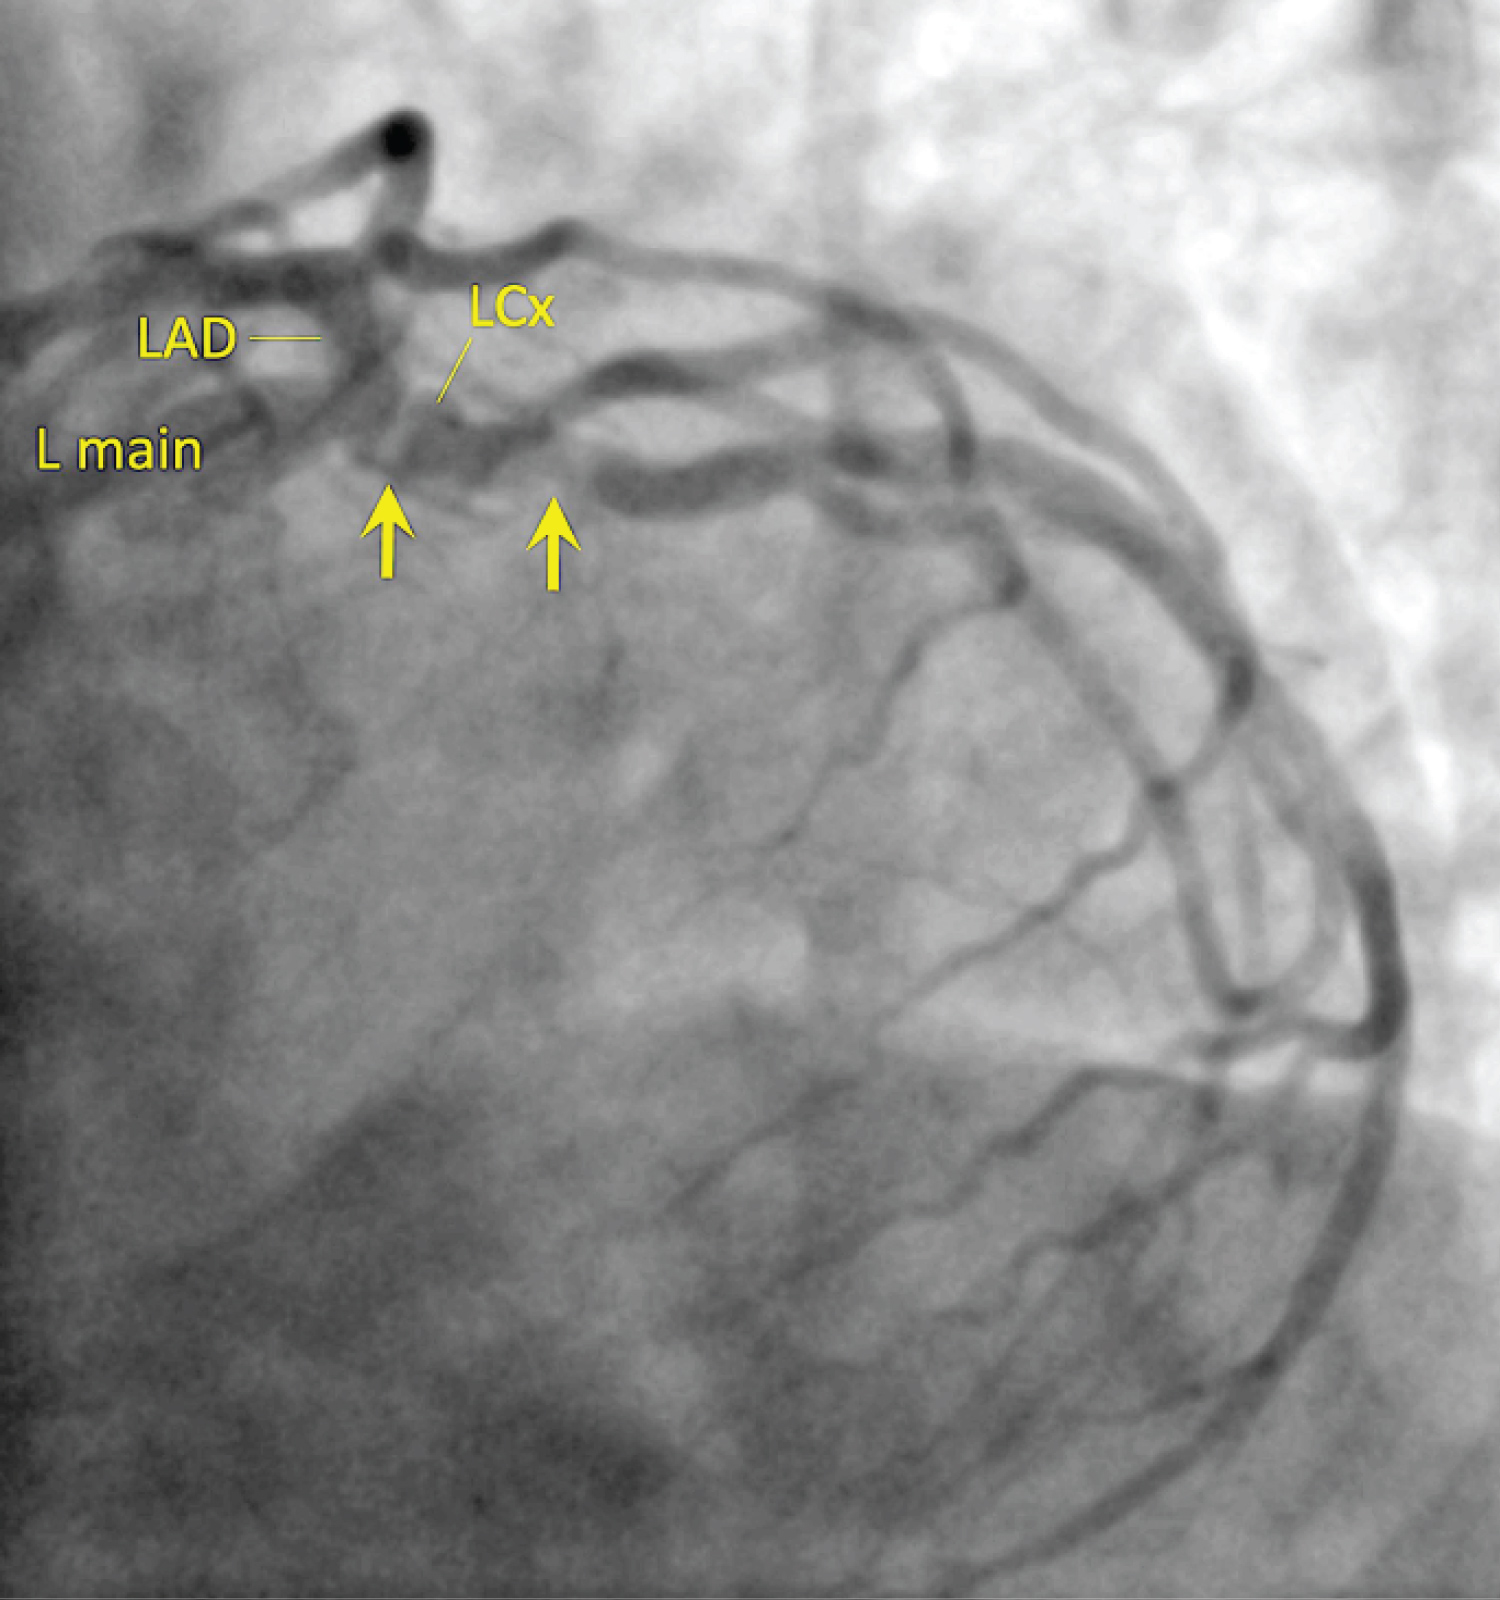

An 81-year-old man with moderate to severe aortic stenosis, hypertension, mild left ventricular hypertrophy, hyperlipidemia, and history of tobacco use presented to the emergency department with subacute-onset intermittent chest pressure at rest, decreased exercise tolerance, and occasional presyncope. At the time of presentation, he was free of symptoms, including chest pain. His blood pressure was 190/91 and he had a grade 3/6 systolic murmur best heard at the right sternal border of the 2nd intercostal space. His presenting electrocardiogram (ECG) showed biphasic T-waves in lead V2 and deeply inverted T-waves in V3 to V6 (Figure 1). These were markedly different from his ECG two years earlier, when his T-waves were upright in these leads (Figure 2 and Figure 3). Serum troponin was negative. A transthoracic echocardiogram re-demonstrated known moderate to severe aortic stenosis and mild concentric left ventricular hypertrophy without evidence of apical hypertrophic cardiomyopathy. Given the concern for hypertensive emergency and unstable angina, he was admitted to the cardiac care unit (CCU), where his blood pressure was lowered with intravenous nitroglycerin and carvedilol, in addition to his outpatient medication, lisinopril. He was also started on other medications for acute coronary syndrome, including aspirin, intravenous heparin, and atorvastatin. The following day, coronary angiography was performed and revealed a 30% distal left main coronary artery stenosis, 95% ostial and 70% mid left circumflex (LCx) artery stenoses (Figure 4), and a 99% ostial right coronary artery (RCA) stenosis (Figure 5). The left anterior descending (LAD) artery had no significant stenosis. Left heart catheterization measurements showed an aortic valve area of 1.1 cm2. After careful consideration of percutaneous and surgical coronary revascularization strategies, the patient was deemed a more suitable candidate for percutaneous coronary intervention (PCI) and underwent successful PCI, with deployment of drug-eluting stents to the LCx and RCA. The T-wave abnormalities on ECG persisted at time of discharge, but the patient's symptoms improved significantly. The T-wave abnormalities ultimately resolved and returned to baseline on his 4 month follow up ECG (Figure 6).

Figure 4: LAO-caudal (extreme "spider") projection showing 95% eccentric, ostial and 70% mid left circumflex (LCx) artery stenoses. View Figure 4